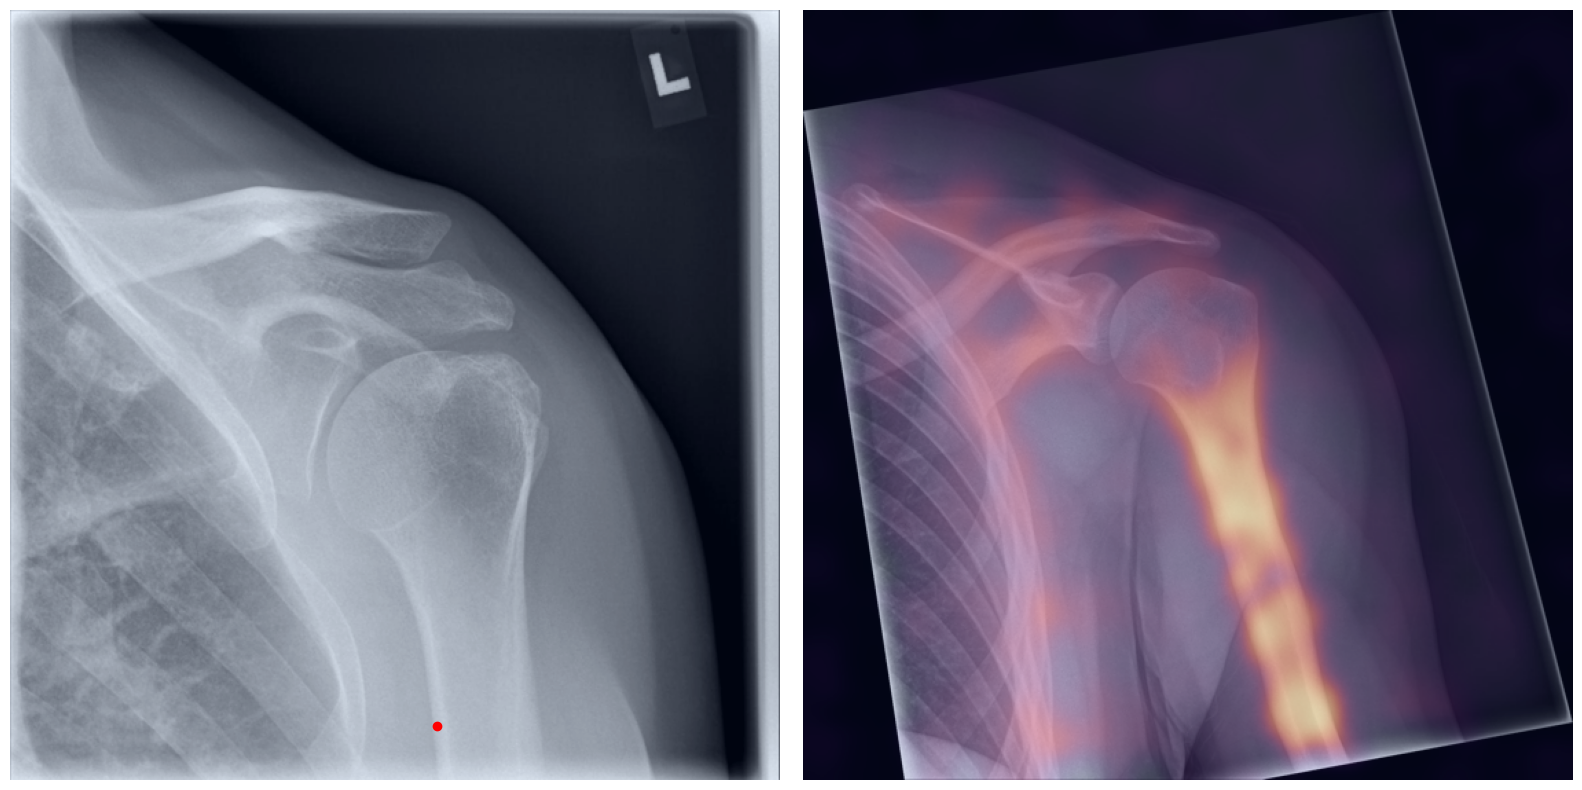

Behind the Curtain: Visualizing the Inner Workings

The process of establishing a dense match between two images relies on abstract feature representations for each position in both the reference and target images. To better understand which information is encoded by the AI, we examined the feature similarities between a specific position within the reference image and the entire target image. Our findings show that the AI captures both semantic and texture features. The matching process utilizes this encoded information, along with precise positional data, to create a reliable mapping between the images.

Hover your mouse over the image to stop automatic transitions.